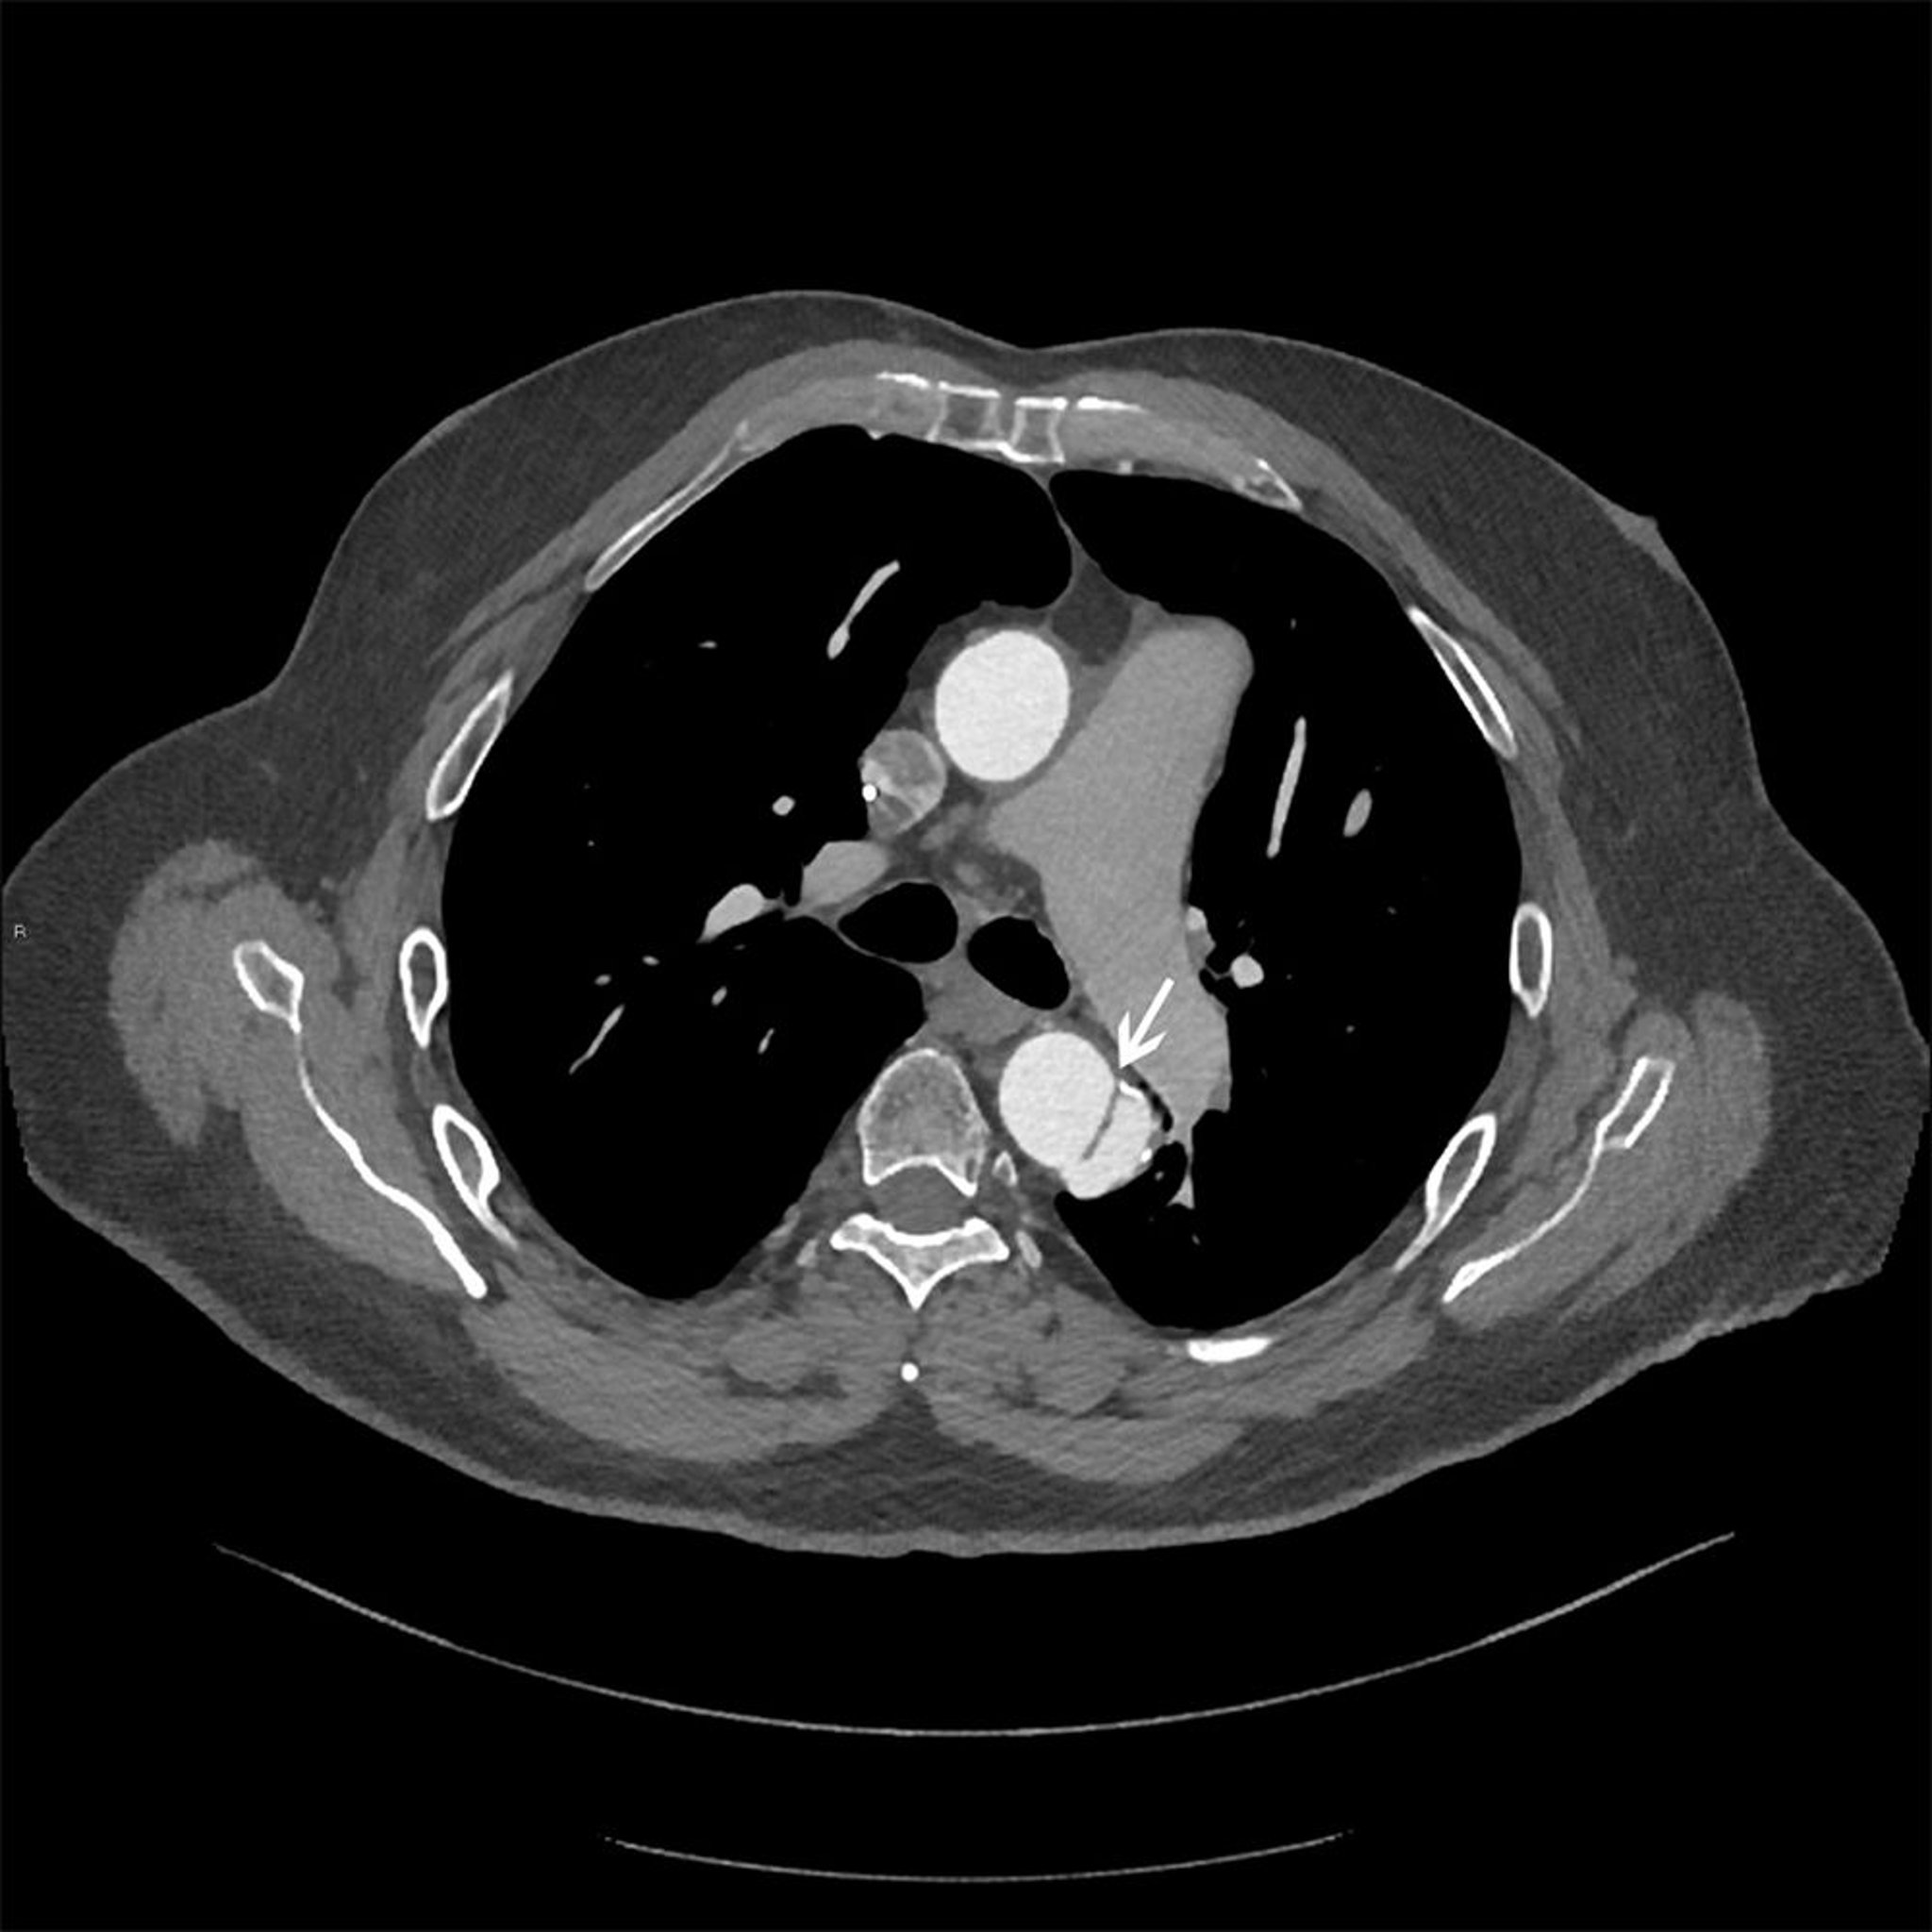

Dissecção da aorta torácica (Stanford tipo B)

Imagem axial do retalho da dissecção (seta branca) na aorta torácica descendente.